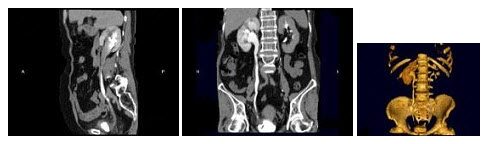

9、多项选择题

男,20岁,右腰部胀痛不适,MRI如图示,下列说法正确的是()

A.右侧肾盂积水

B.右侧输尿管上段扩张积水

C.右侧输尿管走行异常,呈“S”形向中线移位

D.考虑为右侧腔静脉后输尿管

E.考虑为右侧输尿管自身的扭曲